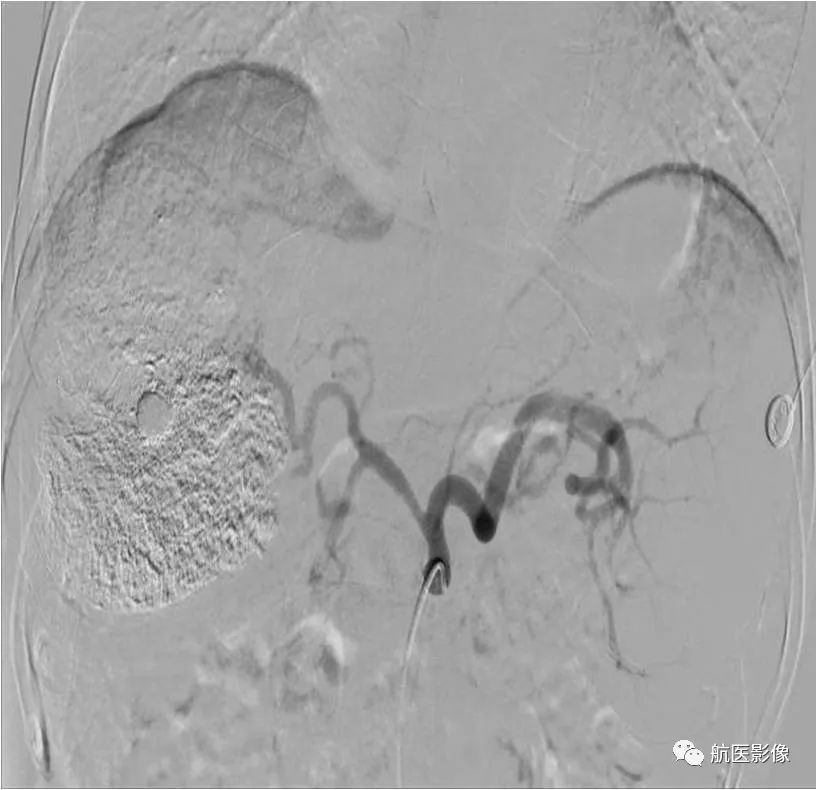

8.肝癌经导管动脉化疗栓塞术(TACE):

将导管超选择性插管至肝癌供血动脉,给予含有化疗药物的碘油乳剂、微球、PVA、明胶海绵等,栓塞肝癌供血动脉分支,阻断血液供给以达到治疗肿瘤的目的。

栓塞前血管造影

栓塞后血管造影(肿瘤供血动脉闭塞)